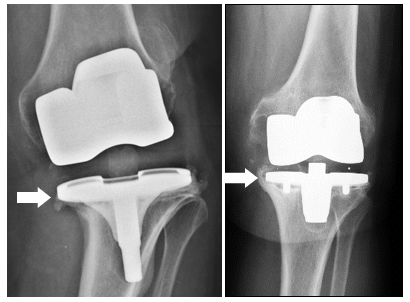

LAS RAZONES COMUNES para reemplazar una prótesis de rodilla incluyen, además de infección, inestabilidad o dolor persistente.

DURANTE UNA NUEVA OPERACIÓN DE RODILLA, muchas veces son necesarios implantes especiales para reemplazar ligamentos defectuosos (con la llamada prótesis acoplada) o para RECONSTRUIR DEFECTOS EN EL HUESO (con aumentos o MATERIAL de reemplazo óseo).